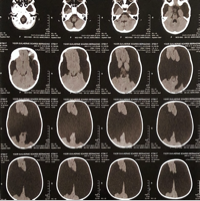

Oi, pexxual!! Me chamo Ygor Guilherme, tenho 2 aninho e nasci com uma malformação rara no cérebro chamada Esquizencefalia Bilateral de Labio Aberto.